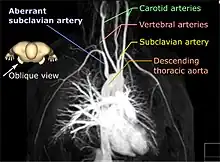

A variation of military projection is used in the video game SimCity A 3D rendered magnetic resonance angiography, shown in an oblique projection in order to distinguish the aberrant subclavian artery

A 3D rendered magnetic resonance angiography, shown in an oblique projection in order to distinguish the aberrant subclavian artery